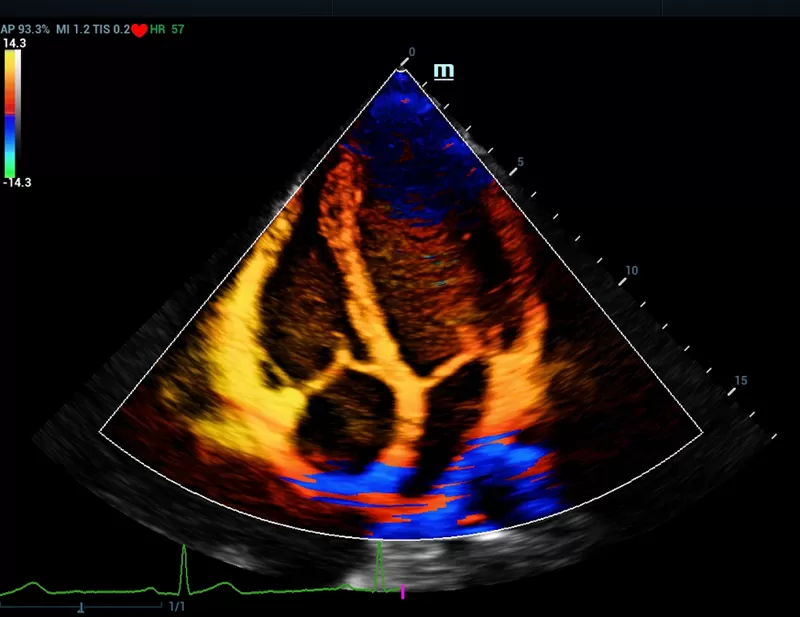

Στη διάθεση σας θα βρίσκονται καταρτισμένοι συνεργάτες μας οι οποίοι θα αναλάβουν να σας παρουσιάσουν τις δυνατότητες του Premium υπερηχογράφου Resona που αποτελεί μια πραγματικά επαναστατική πλατφόρμα, με δεκαπλάσια ταχύτητα σάρωσης χάρις στη μοναδική τεχνολογία zone sonography technology ZST+ που διαθέτει.

Η σειρά Resona ξεχωρίζει όχι μόνο για την κορυφαία απεικονιστική της τεχνολογία αλλά και για τα ευέλικτα εργαλεία ανάλυσης, προσφέροντας ποιότητα απεικόνισης υψηλού επιπέδου και αυξημένη διαγνωστική ακρίβεια.

- HD Scope